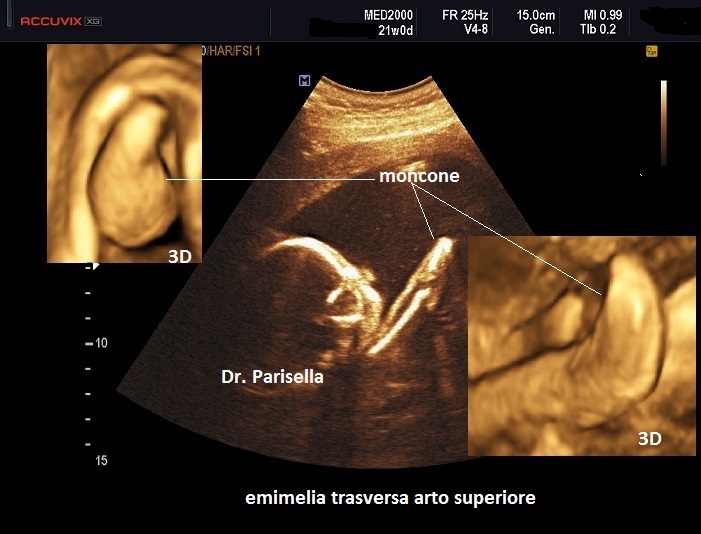

trasversale o trasversa quando manca completamente la parte distale di un arto e può essere presente un moncone che ricorda quello di un'amputazione.